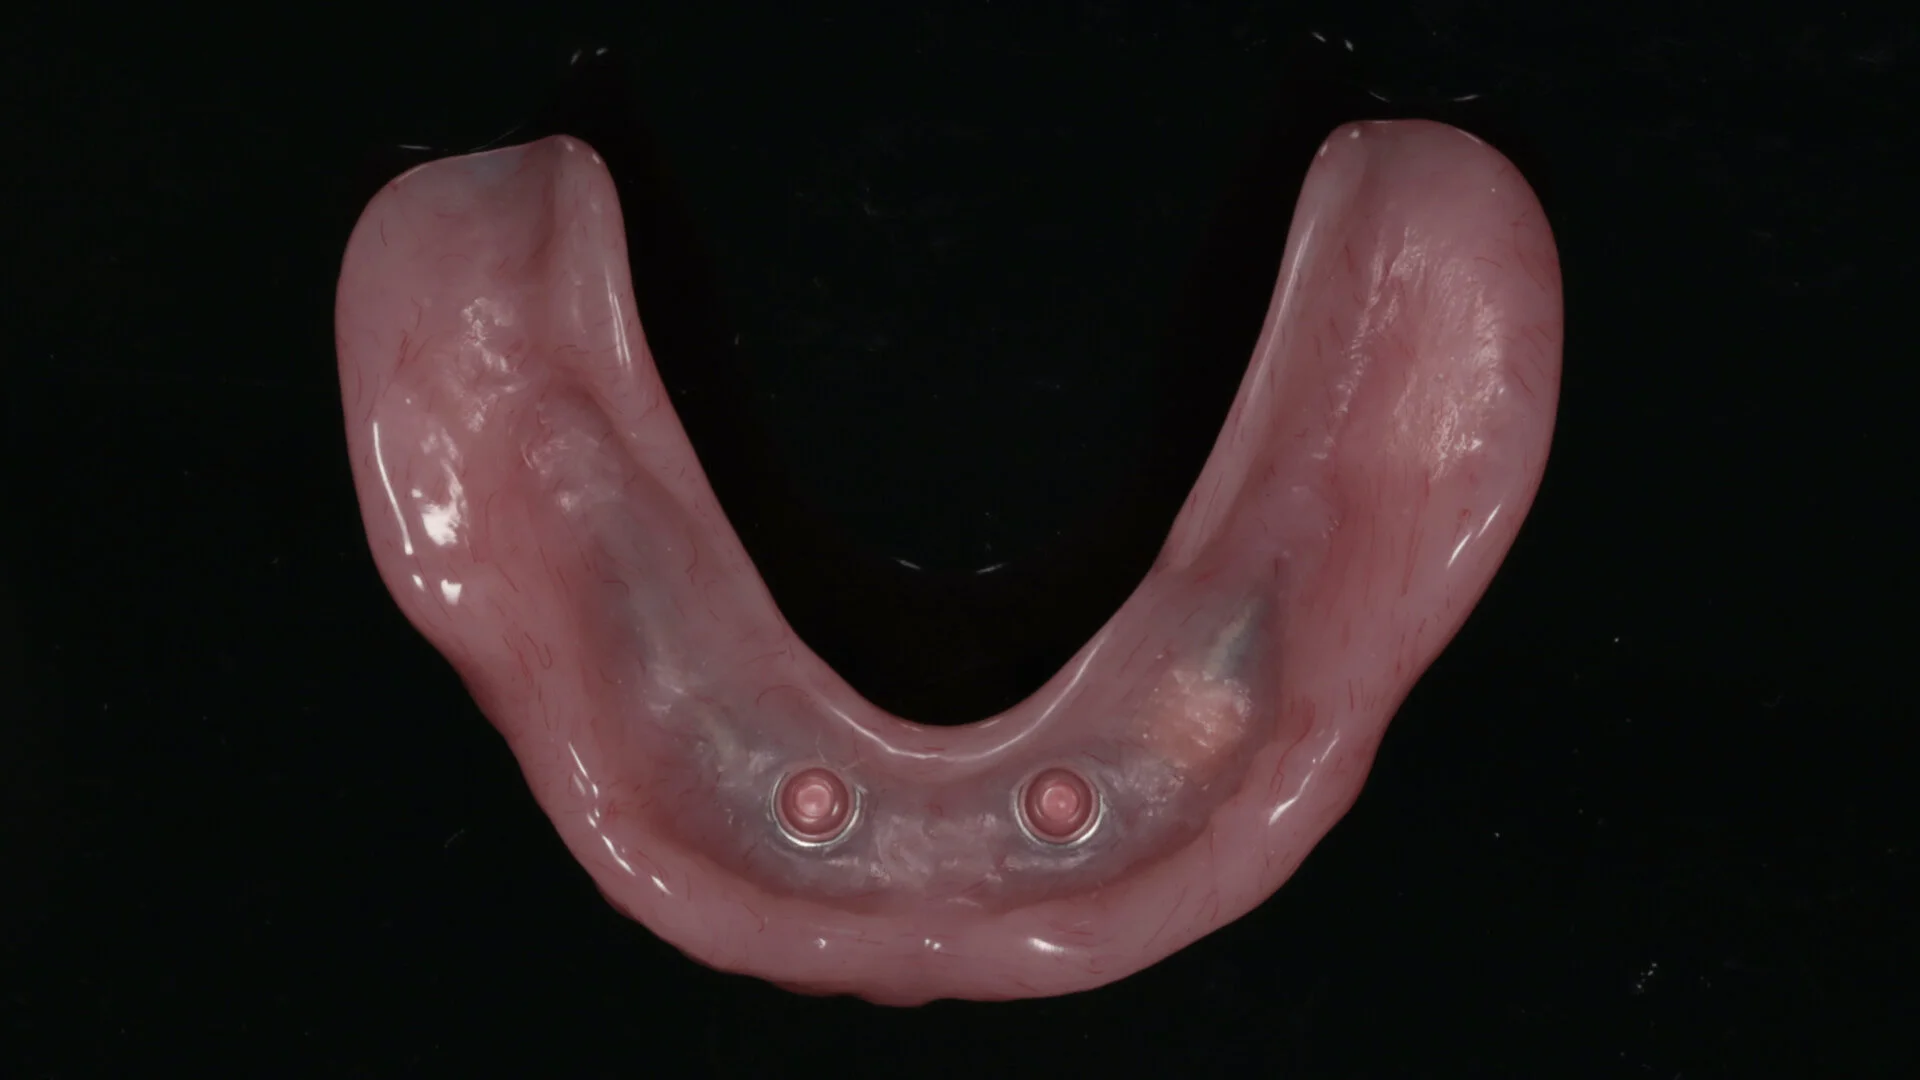

Dentists are seeing an increase in patient edentulism in their practices. A well-designed partial removable dental prosthesis of high quality improves patients’ smiles, chewing and speech function. This treatment modality is often a valid alternative to fixed dental prostheses supported by teeth or implants. In many complete edentulous scenarios, a removable denture stabilised and retained by implants is a preferred outcome compared with implant fixed prostheses. Diagnosis, planning decisions, treatment procedures and clear maintenance protocols are the keys to success in removable prosthodontics.

• Mucosal- and implant-borne removable prostheses